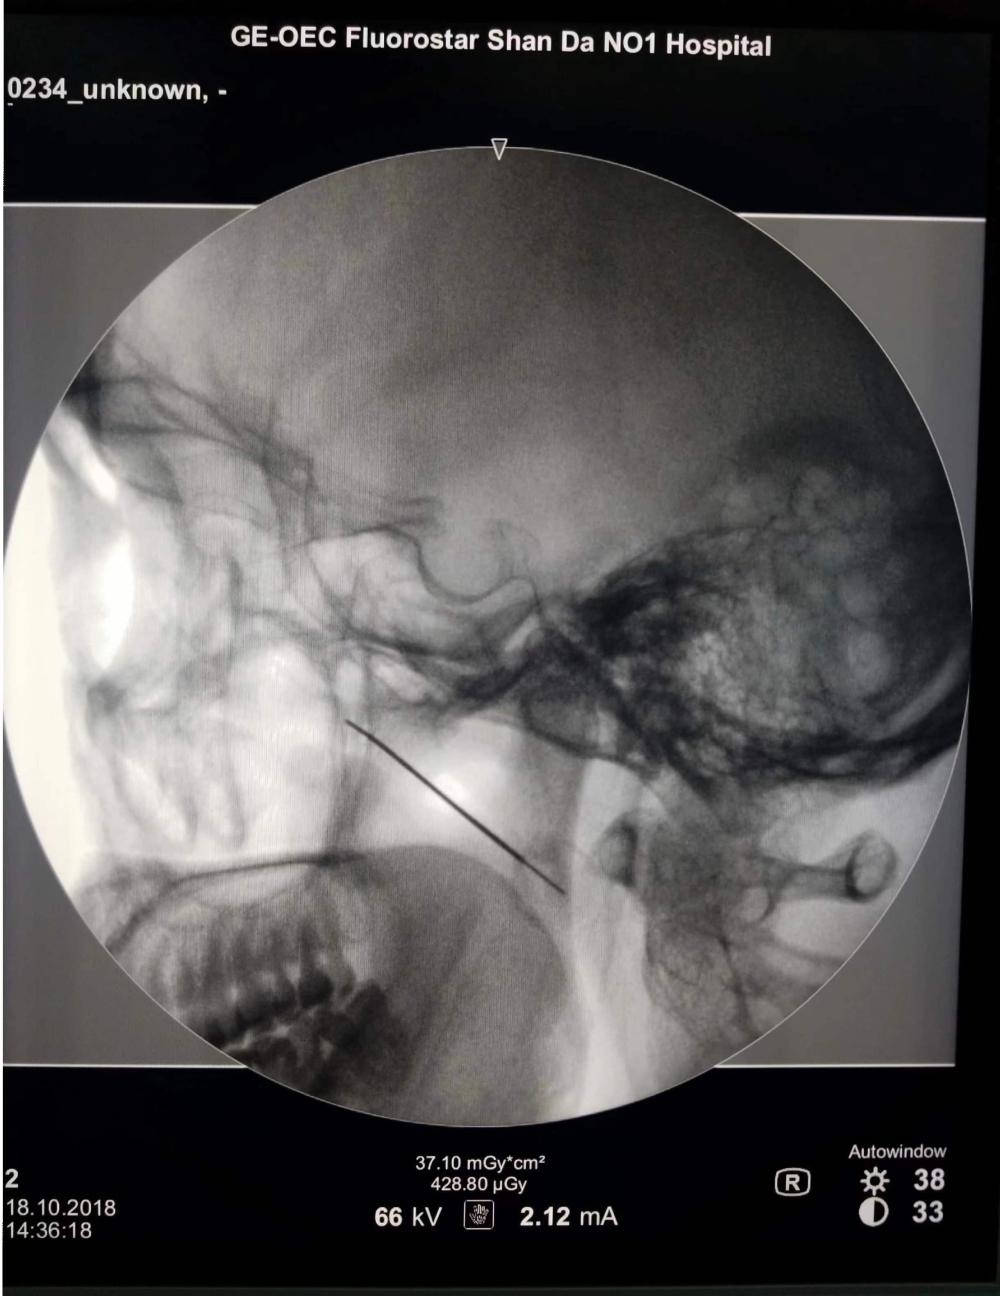

对于三叉神经痛的患者,除了口服药之外,还有更新的微创技术:将一根针穿刺到三叉神经半月节,进行射频热凝或球囊压迫,起到调控神经、治疗疼痛的作用。

射频热凝术,微球囊压迫术